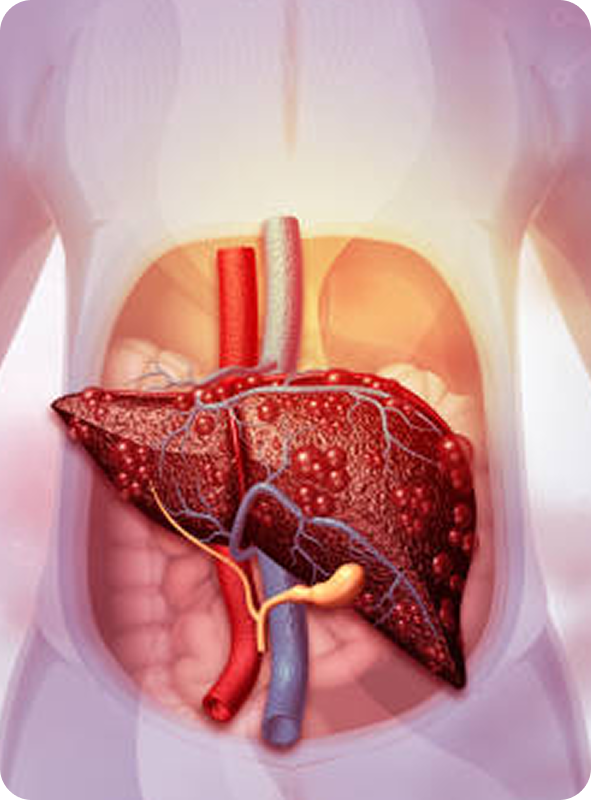

Para mantener un control adecuado de la salud hepática y detectar a tiempo cualquier complicación, es fundamental realizar estudios de laboratorio e imagenología de forma periódica. A continuación, describimos los estudios más importantes, su objetivo y la frecuencia recomendada:

Monitorear la evolución de la enfermedad hepática

Detectar complicaciones tempranas

Ajustar tratamientos a tiempo

Prevenir descompensaciones y hospitalizaciones